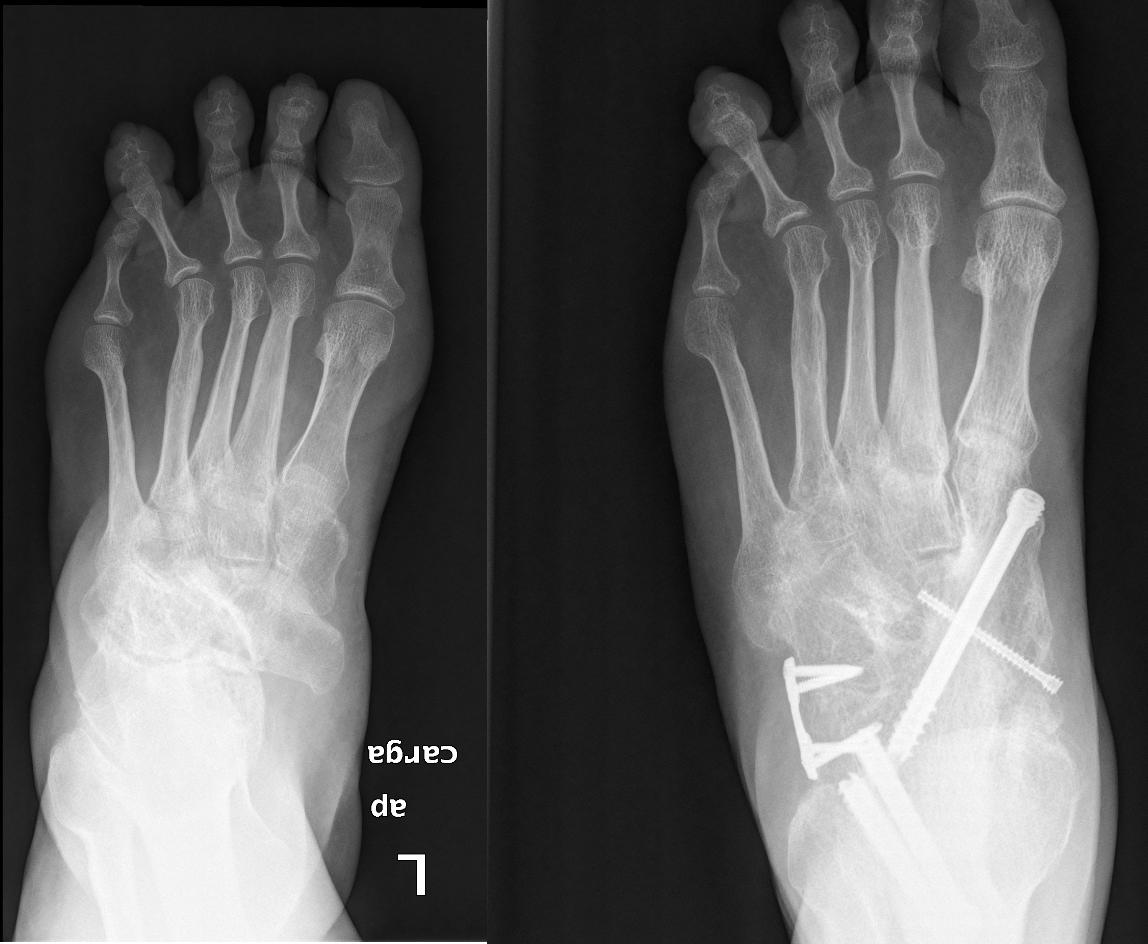

Spontaneous Osteonecrosis of the Tarsal Navicular in an Adult Mueller

MüllerWeiss Disease of the Tarsal Navicular An Idiopathic Case The Mallory Weiss Navicular 1 its prevalence seems to be rare with regional variations in frequency. 1 the definite cause is still unknown. This syndrome is distinct from. Mallory Weiss Navicular.

Mueller Weiss Syndrome A Missed Cause of Mid Foot Pain Mallory Weiss Navicular 1 the definite cause is still unknown. 1 its prevalence seems to be rare with regional variations in frequency. This syndrome is distinct from. Mallory Weiss Navicular.

MüllerWeiss Disease of the Tarsal Navicular An Idiopathic Case The Mallory Weiss Navicular 1 its prevalence seems to be rare with regional variations in frequency. This syndrome is distinct from. 1 the definite cause is still unknown. Mallory Weiss Navicular.